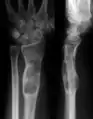

X-ray showing calcified enchondromas localized in finger a 37-year-old patient affected with Ollier disease

X-ray showing enchondromas localized in the humerus of a 37-year-old patient affected with Ollier disease